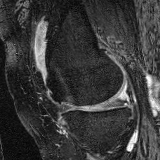

Knee MRI experiment: We test our method on 3D knee MRIs from the Osteoarthritis Initiative (OAI) 111https://nda.nih.gov/oai/ and corresponding segmentations of femur and tibia as well as femoral and tibial cartilage [1]. From a total of 507 labeled images, we use 200 for training, 53 for validation, and 254 for testing. To test registration performance we use 10,000 random image pairs from the test set. All images are affinely registered to an atlas built from the training images, resampled to isotropic spacing of 1mm, cropped to and intensity normalized to [0,1]. In addition, right knee images are flipped to be consistent with left knees. For training, the loss weights are , , and based on approximate hyper-parameter tuning. Note that when computing from the displacements, the image coordinates are scaled to [-1, 1] for each dimension following the convention in the interpolation function of PyTorch.

Results: All trained networks are evaluated using Dice overlap scores between predictions and the manual segmentations for the segmentation network, or between the warped moving segmentations and the target segmentations for the registration network. Tabs. 1 and 2 show results for the knee and brain MRI experiments respectively in Dice scores (%). Fig. 2 shows examples of knee MRI registrations and brain MRI segmentations.

Qualitative results: DA achieves more anatomically consistent registrations than the mono-networks on the knee (Fig. 2) and Brain MRI samples (see supplementary material).